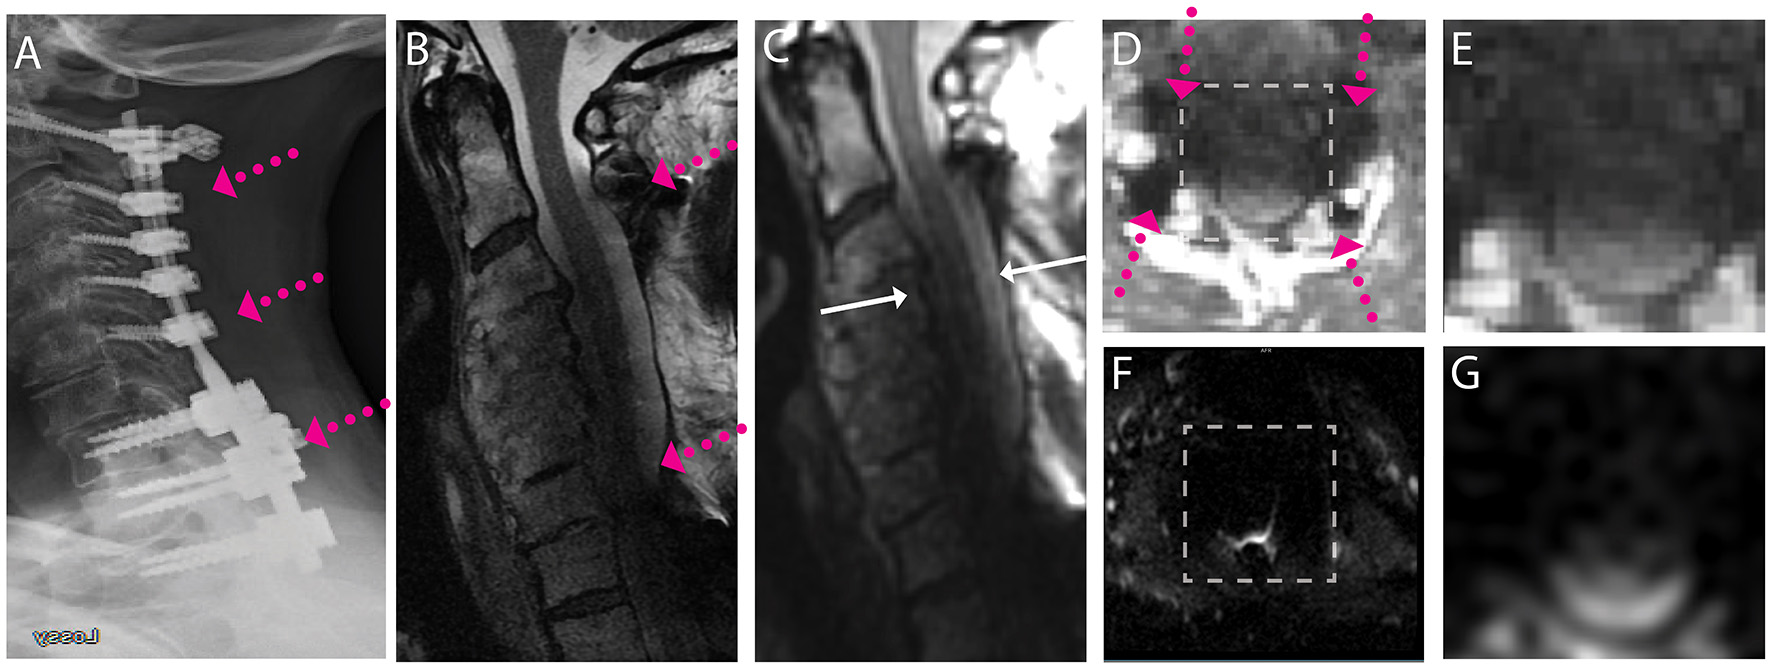

Exemplary sample images of instrumented fusion CSM subjects are provided in Figures 1–4. For all cases, the artifact reduction attained by the utilization of multi-spectral imaging techniques, which enables geometrically accurate morphological assessment and segmentation of the cord, is evident when comparing panels (B, conventional) and (C, 3D-MSI). The importance of multi-spectral DW methods is evidenced in panels (F, FOCUS EPI) and (G, DW-MSI), where the cord region is completely obscured by artifact in the conventional single-shot EPI (F) for all example subjects. This complete inability for FOCUS EPI to collect cord diffusion data near instrumented cord regions was observed for all study participants.

Representative images of a CSM subject with extensive posterior fusion hardware used to treat cord compression and severe stenosis across the cervical and high thoracic spine. (A) Radiograph illustrating anterior posterior extensive fusion plane/screws (pink arrows). (B) Conventional MARS T2 weighted image, demonstrating substantial image distortions across the cervical spine. (C) Isotropic (1.2 mm) MAVRIC SL 3D-MSI T2 weighted image with image distortions but substantial image shading due to hardware induced B1 field perturbations. (D) Axial reformat of isotropic MAVRIC SL image location indicated by white arrows in (C). (E) Zoomed MAVRIC T2w image in across box indicated in (D). (F) Conventional single-shot b = 0 EPI image (FOCUS). (G) DW-MSI T2w (b = 0) within indicated box. The DW-MSI imaging approach was unsuccessful in this scenario, due to the substantial signal degradation induced by the B1 shading artifact.

Finally, Figure 4 provides a scenario where even the advanced artifact mitigation of DW-MSI is unable to produce useful diffusion-weighted imaging. This subject was treated with posterior fusion hardware spanning the cervical and superior portion of the thoracic spine. The geometry and material properties of this hardware generated substantial B1 magnetic field perturbations, which are known to cause shading confounds, even within 3D-MSI MRI that have addressed image distortion artifacts (38). The effect of this shading is clearly evident on both the MARS (Figure 4B) and 3D-MSI T2w images (Figure 4C). The impact of this shading on DW-MSI signal integrity within the cord region is clearly evidenced in Figure 4G, where minimal cord signal is evident within the DW-MSI b = 0 image. This effect impacted a small number (3/38) of the study datasets and was observed only in cases with substantial superior-inferior coverage of posterior hardware. Though DW-MSI ADC maps were still capable of being collected in these cases, the number of measures that passed quality-control measures were reduced.